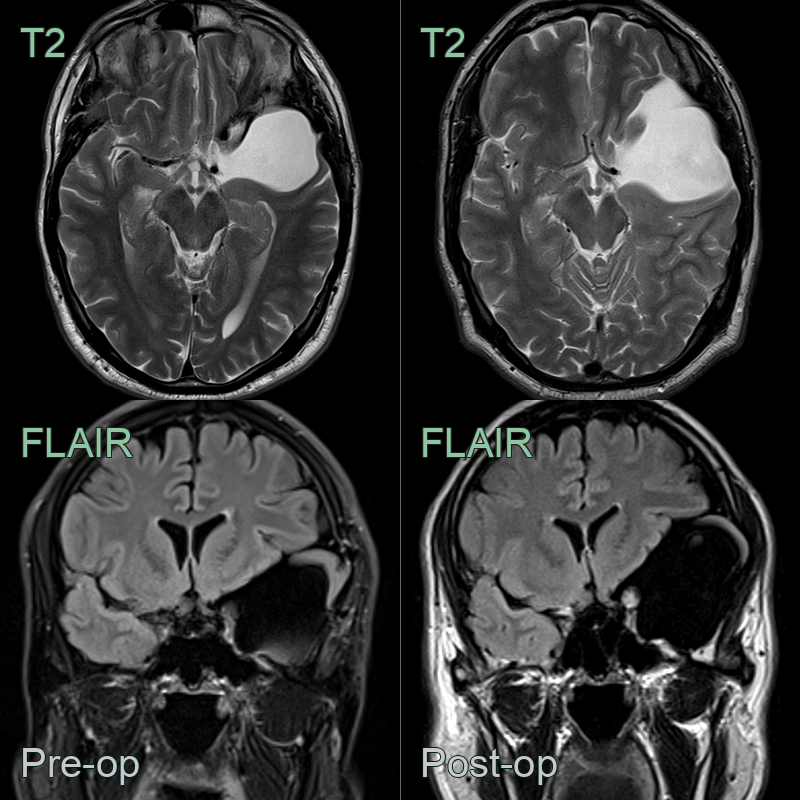

- Usually no treatment is necessary

- If responsible for symptoms, they can be fenestrated to allow free communication of CSF between the cyst and the subarachnoid space